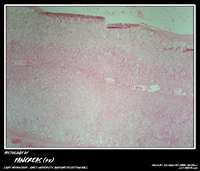

PANCREASE

Click to enlarge